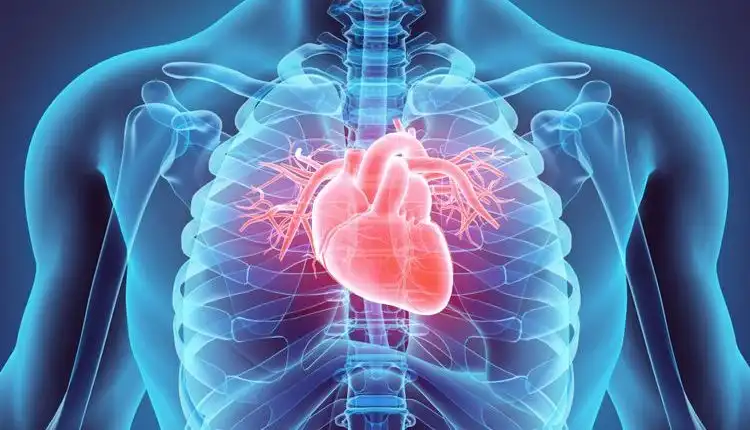

Apa itu Gangguan Katup Jantung?

Gangguan Katup Jantung adalah kondisi ketika katup jantung tidak berfungsi dengan baik. Manusia memiliki empat katup jantung, yaitu katup mitral, trikuspid, pulmonal, dan aorta. Tugas katup-katup ini adalah memastikan darah mengalir ke arah yang tepat melalui empat ruang jantung dan seluruh tubuh. Pada gangguan katup jantung, salah satu atau lebih katup mungkin mengalami kelainan.